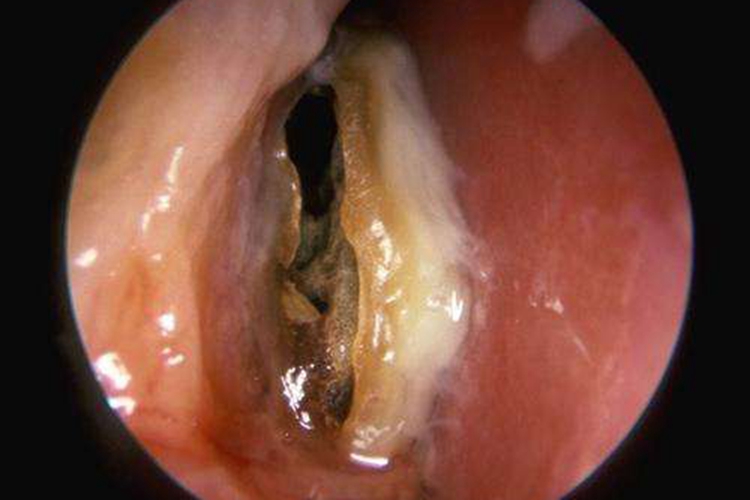

鼻子干酪样分泌物在临床见于干酪性鼻炎,症状表现为进行性鼻塞,经常流出稠厚脓涕,味奇臭,伴有嗅觉减退,有少量鼻出血。体格检查可发现外鼻变形,一侧鼻腔内充满发臭、腐败干酪样物质,清除此类物质后有时可发现息肉或肉芽,下鼻甲或中鼻甲可被侵蚀,筛窦与上颌窦内壁可被破坏,窦内亦可有同样干酪样物积留。